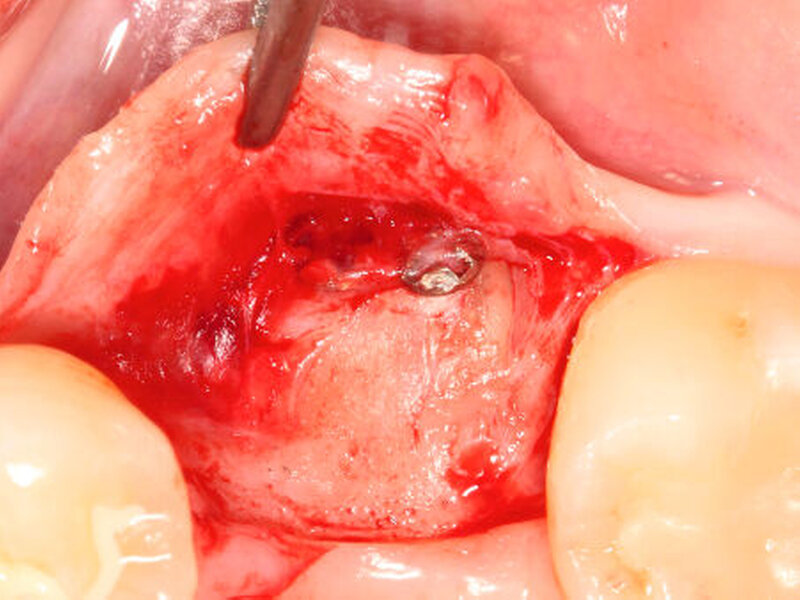

In einem ersten Pilotversuch beim Menschen konnte das Verfahren der autogenen Wurzeltransposition erfolgreich bestätigt werden. Hierbei diente ein retinierter oberer Weisheitszahn als Quelle für das Wurzelaugmentat, das zur lateralen Augmentation einer Schaltlücke im Unterkiefer analog zu dem oben genannten chirurgischen Verfahren eingesetzt wurde. Nach einer Heilungsphase von sechs Monaten zeigten sich deutlich klinische Anzeichen für eine nahezu vollständige Ersatzresorption der Zahnwurzel durch eine mineralisierte Hartsubstanz. Die horizontale Verbreiterung des ehemaligen Defektbereichs ermöglichte eine prothetisch orientierte, regelrechte Implantatinsertion (Abbildungen 5a und b).

Neben retinierten, impaktierten, verlagerten oder überzähligen Zähnen werden im nächsten Schritt auch endodontisch behandelte Zähne ohne Anzeichen einer lokalen Pathologie für die Gewinnung von Zahnwurzelaugmentaten klinisch untersucht (Abbildungen 6a und b).

Neben einer Transposition in bereits bestehende Defektbereiche könnte die Zahnwurzel auch zur direkten Augmentation defizitärer Extraktionsalveolen (zum Beispiel Schalentechnik bei Dehiszenzdefekten) Verwendung finden (Abbildung 6c).